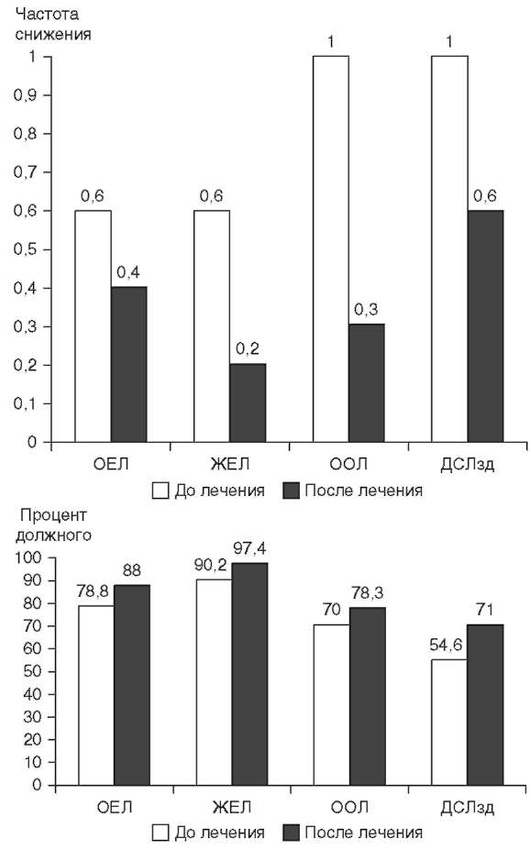

Исследование функциональных показателей внешнего дыхания.

Характер и степень изменения ФВД при ЭТА зависят от рентгенологического варианта заболевания. У половины больных ЭТА выявляется резкое и значительное снижение ОЕЛ с перестройкой ее структуры по рестриктивному типу, достоверно более выраженной у рентгенположительной группы больных по сравнению с рентгенотрицательной группой. Эластическая отдача легких умеренно увеличивается. ДСЛ снижается как в устойчивом состоянии, так и при задержке дыхания. При бериллиозе ее снижение может наблюдаться за несколько лет до появления рентгенологических изменений (Clinical guideline for the diagnosis of Berillium, 2015).

Рестриктивный синдром при рентгенотрицательном варианте ЭТА выражен в меньшей степени, чем при рентгенположительном ЭТА, и ведущим является нарушение ДСЛ. Так, при воздействии органических растворителей (хлорированных этиленов: трихлорэтилена, трих-лорэтана, винилхлорида, ароматических углеводородов) ЭТА может протекать как рентгенотрицательный вариант с рестриктивным синдромом и снижением ДСЛ. Следует отметить, что у больных ЭТА может выявляться обструктивный синдром, обусловленный развитием ОБ (Орлова Г.П., 2019). Рестриктивного синдрома при ингаляционных лихорадках может не быть, или он выражен относительно слабо (Ahsan S.A. et al., 2009; Shimizu T. et al., 2012; Greenberg M.I. et al., 2015). Результаты исследования ФВД и легочного газообмена могут влиять на терапевтическую тактику, но не позволяют дифференцировать ЭТА от других фиброзирующих альвеолитов.

Зависит от сроков установления диагноза и быстроты устранения этиологического фактора. Своевременная и адекватная терапия может привести к полному или частичному (сохраняется снижение ДСЛ) выздоровлению. Лечебные мероприятия на поздних стадиях заболевания малоэффективны, и прогноз, как правило, неблагоприятный. При Ардистил-синдроме в случае развития ОП прогноз благоприятный (улучшение отмечается в течение одного года). При ОБ с ОПфиброзе прогноз серьезный - у 17% больных заболевание прогрессирует даже на фоне терапии системными ГК (Solé A. et al., 1996; Romero S. et al., 1998). Прогноз ЭТА от нейлонового флока более благоприятный (рис. 2.32) - вывод больных из вредных условий труда и системная ГК терапия может существенно улучшить прогноз (Glazer C.S., Maier L. Eur. Respir. Mon., 2009). ЭТА от воздействия оксида индий-олово характеризуется прогрессирующим пневмофиброзом с развитием вторичного ЛАП даже после прекращения контакта с этиологическим фактором (Cummings K.J. et al., 2016). Прогноз лекарственно-индуцированного ЭТА описан в соответствующей главе.